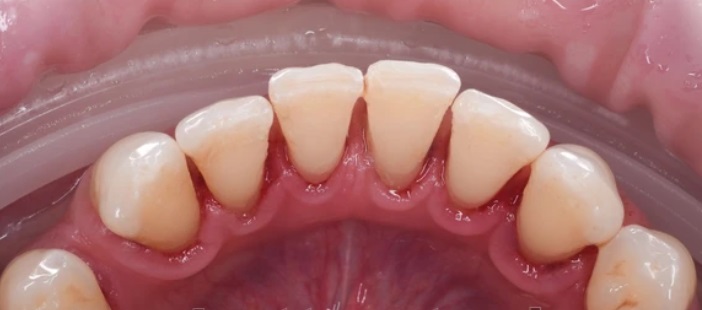

Проблема

Пациент обратился с жалобами на зубной налет, наличие зубного камня на передних зубах нижней челюсти.

Решение

Проведена профессиональная гигиена полости рта (AirFlow). Удален зубной камень и налет. Пациент доволен!